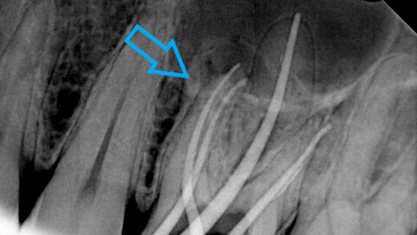

Η φλεγμονή του δοντιού αποδόθηκε σε πιθανό επανατερηδονισμό λόγω ατελούς έμφραξής του. Εξαιτίας του ανεπαρκούς σφραγίσματος του δοντιού, τα μικρόβια πέρασαν στο εσωτερικό του δοντιού (ρίζα) και “μόλυναν” κατ΄ επέκταση την απονεύρωση του δοντιού. Ακτινογραφικά διαπιστώθηκε η ατελής απονεύρωση στο επάνω μέρος της ρίζας του δοντιού. Επίσης στην ακτινογραφία διακρίνεται και η μη ερμητική απονεύρωση του δοντιού σε όλο το μήκος της ρίζας του δοντιού.

Τα προαναφερθέντα διαγνωστικά στοιχεία σε συνδυασμό με την περιοδοντική νόσο της ασθενούς οδήγησαν στην εμφάνιση αλλοίωσης στο άκρο της ρίζας του δοντιού, η οποία και κρίθηκε σκόπιμο να αντιμετωπιστεί.

Μετά από συνεννόηση με τον ασθενή αποφασίστηκε η επανάληψη της ενδοδοντικής θεραπείας (απονεύρωσης). Ακολούθως έγινε τοποθέτηση του ελαστικού απομονωτήρα, η διάνοιξη του δοντιού και η αφαίρεση του παλιού εμφρακτικού υλικού από τις ρίζες.Επιπρόσθετα εντοπίστηκε και παρασκευάστηκε και 4ος ριζικός σωλήνας, ο οποίος δεν είχε επεξεργστεί στην πρώτη ενδοδοντική θεραπεία ( απονεύρωση ) του ασθενούς.